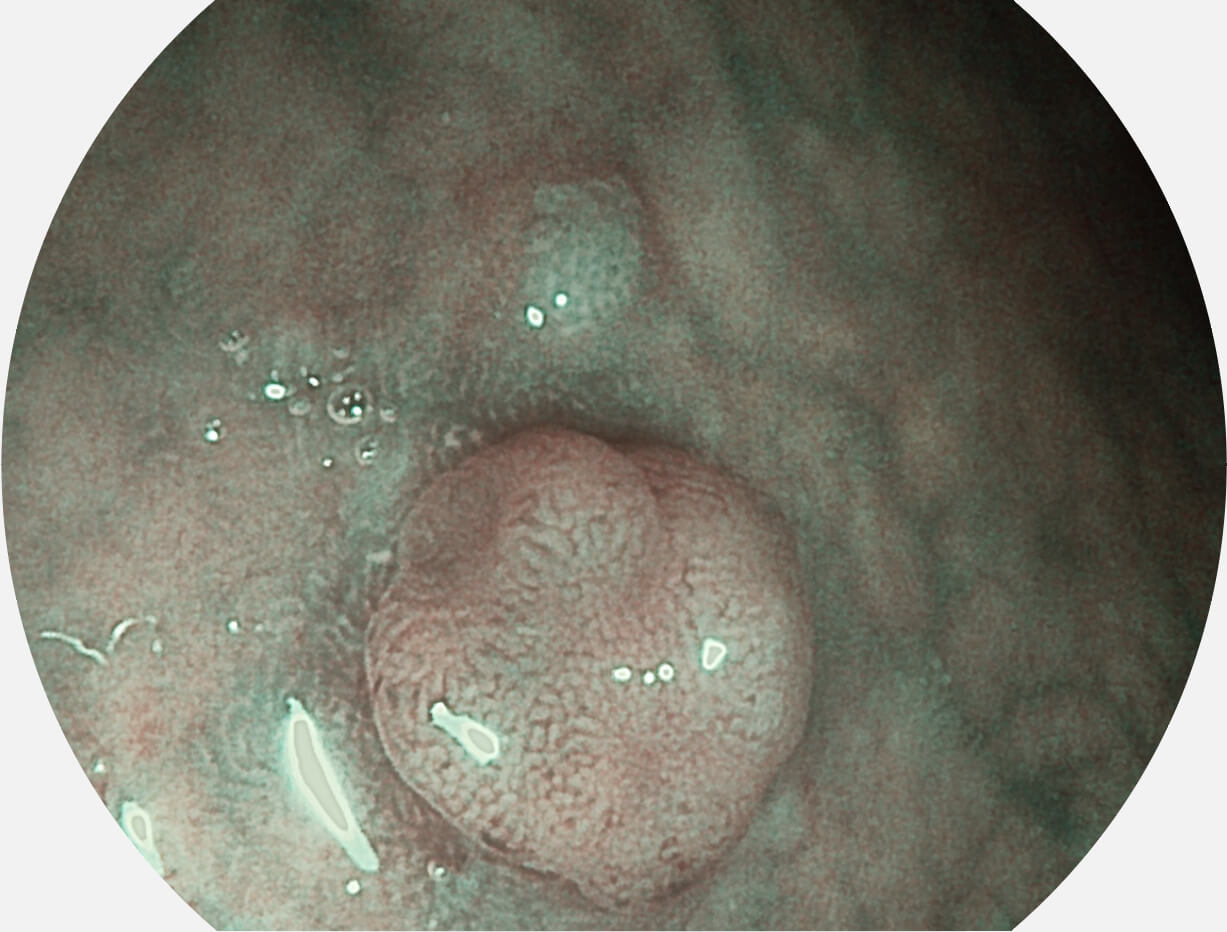

• 白光圖像 VIST圖像